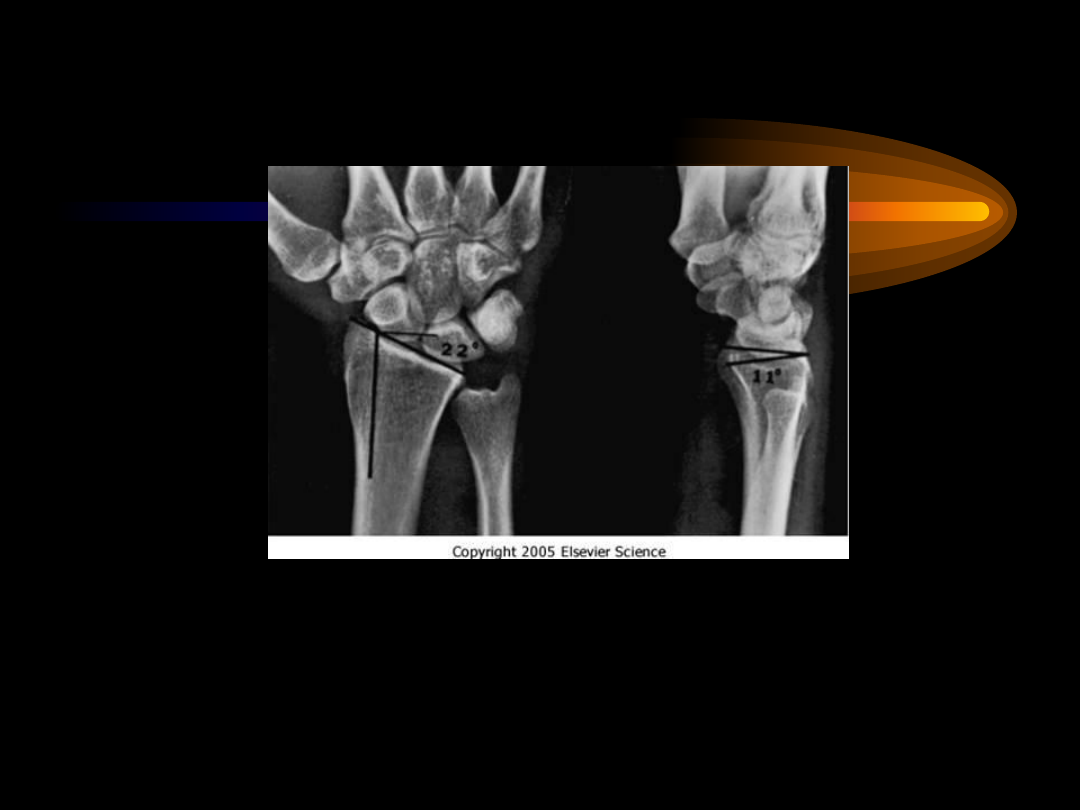

The   anteroposterior  radiograph  on  the  left illustrates normal radial

inclination of  approximately 22  degrees.  The lateral radiograph  on

the  right illustrates normal volar tilt of  the distal articular surface  of

approximately 11 degrees.